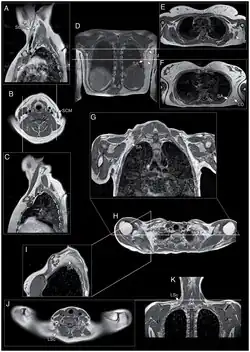

Medical imaging (CT and MRI) have shown muscle involvement not readily apparent otherwise[37]

- A single MRI study shows the teres major muscle to be commonly affected.[38]

- The semimembranosus muscle, part of the hamstrings, is commonly affected,[25][84][85] deemed by one author to be "the most frequently and severely affected muscle."[2]

- Of the quadriceps muscles, the rectus femoris is preferentially affected[84]

- Of the gastrocnemius, the medial section is preferentially affected;[84][85]

- The iliopsoas, a hip flexor muscle, is very often spared.[85][2]

- Magnetic resonance imaging (MRI) is sensitive for detecting muscle damage, even in mild cases. T1-weighted MRI imaging can visualize fatty infiltration of muscles, and T2-weighted MRI imaging can visualize muscle edema. MRI can help differentiate FSHD from other muscle diseases based on the pattern of muscles involved, directing genetic testing.[37][38]